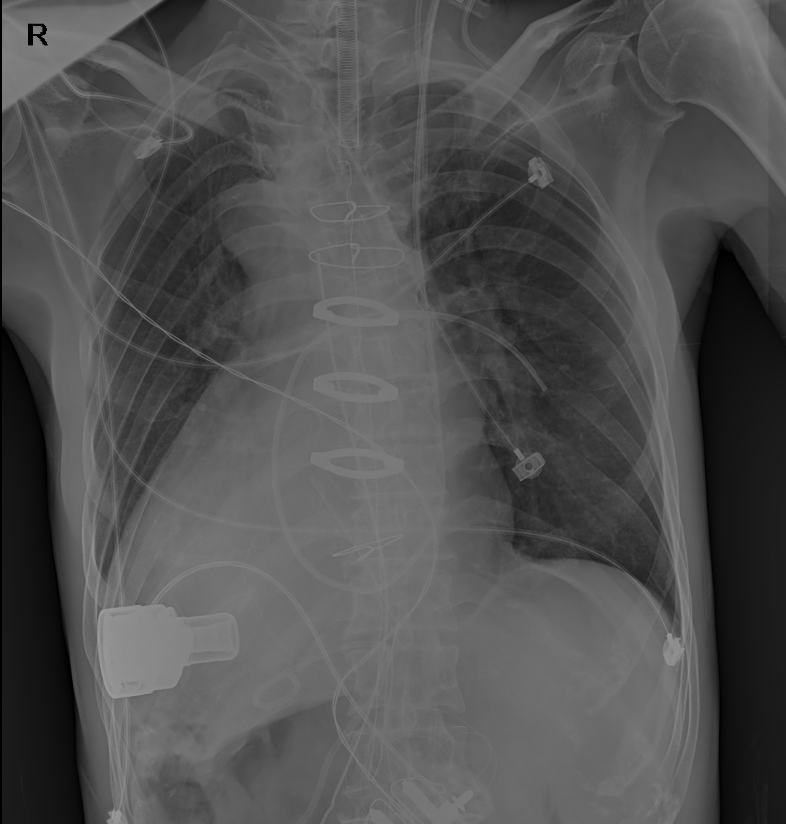

患者术后DR胸片

“镜面人”又称“镜子人”或“镜像人”,发生率大约为百万分之一,临床上通常表现为胸腔、腹腔器官及解剖结构的完全左右反位。这种反位通常不影响脏器生理功能,但是“镜面人”一旦患病就会给治疗特别是手术治疗带来巨大障碍。据张大发主任介绍,左心室辅助装置植入术本就属于难度最高的四类心脏手术,而患者的心脏长在右边,这种镜面右位心让手术视野完全相反,手术操作必须反过来进行,每一步都像在做脑筋急转弯,使手术难度和风险增加了数倍。